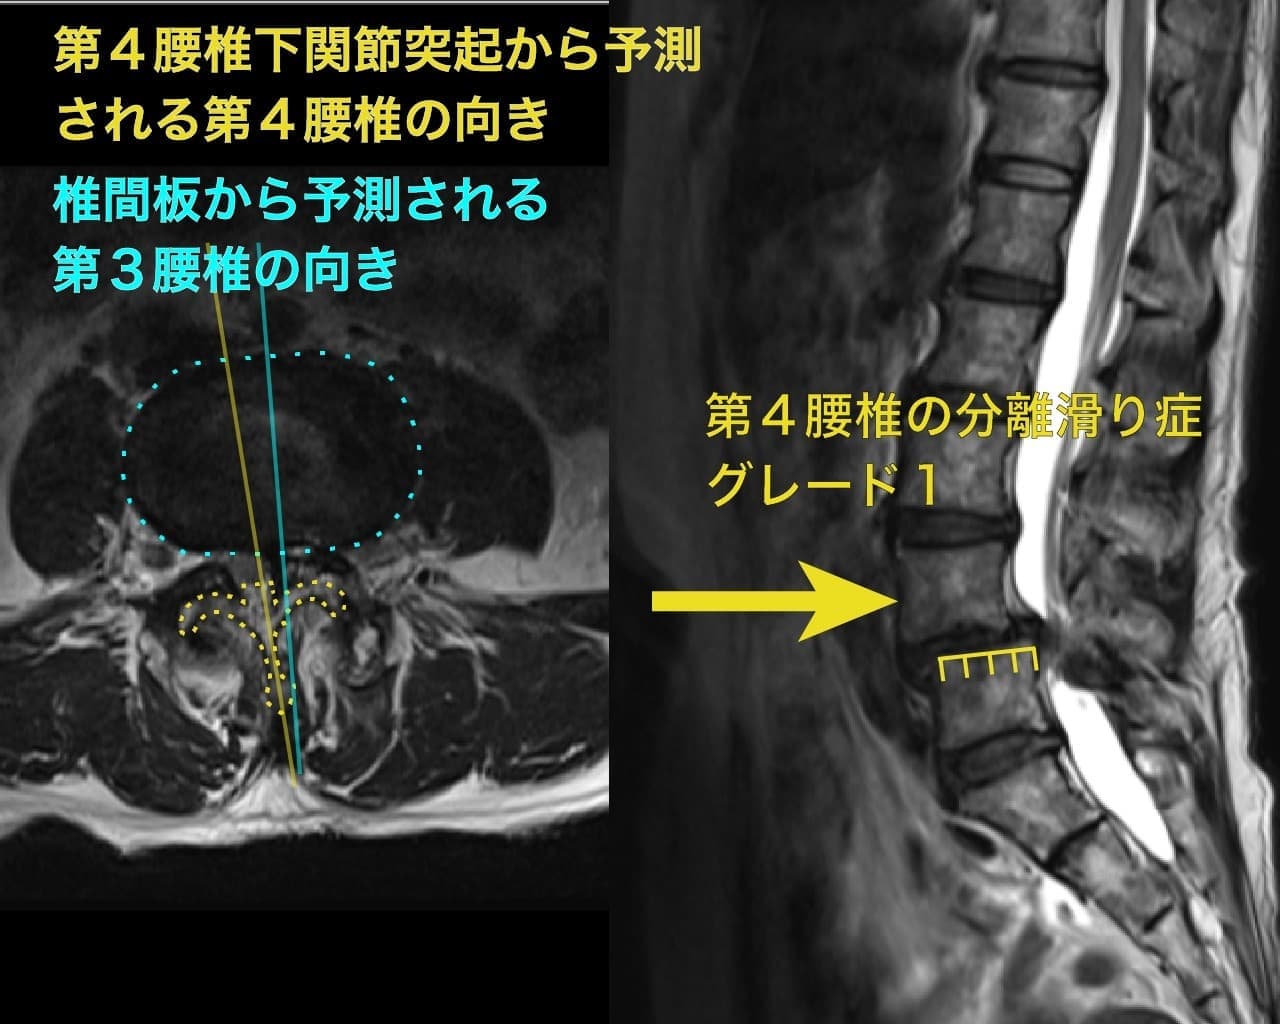

腰椎分離すべり症 脊柱管狭窄症

症例:腰椎分離すべり症 脊柱管狭窄症 50代女性

分離すべり症があり、25%ギリギリなので恐らくグレード1でしょうか。

ただし、脊柱管の圧迫は強く歩行距離も調子が悪いとすぐに休まないといけない程度でした。

確かに滑り症はあるものの、腰椎の回旋を示唆する初見が触診でも画像上でも見られたため、回旋状態を改善すると歩行距離は伸びていきました。

分離滑り症と腰椎の回旋が神経痛を起こす原因はこちらで説明しました